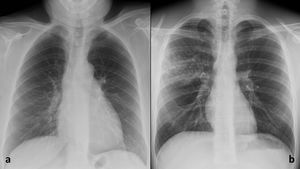

Probabilidad de neumonía COVID-19 según las radiografías, basada en la clasificación de la Sociedad Británica de Radiología Torácica5 (figs. 4-5).

Probabilidad de afectación en cada zona pulmonar. Para ello, se analizaron las radiografías de tórax tras dividir la imagen en 6 zonas pulmonares (fig. 1).

Dos radiólogos con 14 y 11años de experiencia de la Unidad de Radiología de Urgencias evaluaron la probabilidad de afectación (sí/no) de cada zona pulmonar en las radiografías de tórax de 480 pacientes utilizando tanto radiografías como imágenes de tomosíntesis 3D. De ellos, se seleccionaron aquellos casos en los que los dos radiólogos coincidieron en su veredicto de afectación (sí/no) para todas las zonas pulmonares (fig. 1). Así, el grupo de radiografías patológicas estaba formado por 56 casos con concordancia en la distribución de las opacidades pulmonares. Cuando los radiólogos discreparon en la determinación de la probabilidad de neumonía COVID-19, se tomó una decisión final por consenso. Además, se añadió una muestra aleatoria de 57 casos con radiografías de tórax sin opacidades según ambos radiólogos, que constituyeron el grupo de radiografías normales (fig. 2).

Además, para determinar si la contribución de la evaluación de la imagen de IA fue favorable o desfavorable, se contabilizó el número de veces que cambiaba la interpretación del lector en la «probabilidad de afectación de cada zona pulmonar», así como el número de veces que este cambio concuerda con el estándar de referencia y el número de veces que discrepa. Además, para determinar si sería útil disponer de la imagen IA en los casos de neumonía con manifestaciones radiológicas sutiles, se hizo una distinción para la neumonía COVID-19 con puntuación Brixia en el grupo de 56 pacientes con radiografías patológicas. Para evaluar la puntuación Brixia, la radiografía de tórax se divide en seis zonas pulmonares (fig. 1a), y las opacidades de cada zona se cuantifican como 0: normal; 1: opacidades en vidrio deslustrado (OVD); 2: OVD y consolidaciones con predominio de OVD; 3: consolidaciones con o sin OVD, con predominio de consolidaciones. La puntuación oscila entre 0 y 18 puntos7. Se comparó el rendimiento diagnóstico para una puntuación brixia inferior o igual a 9 puntos con una puntuación superior a 9 puntos, según la valoradión del radiólogo de urgencias con 14 años de experiencia, ya que el punto medio de gravedad según la puntuación del índice Brixia es de 9 puntos (fig. 2). Las frecuencias de este recuento se analizaron de forma descriptiva.